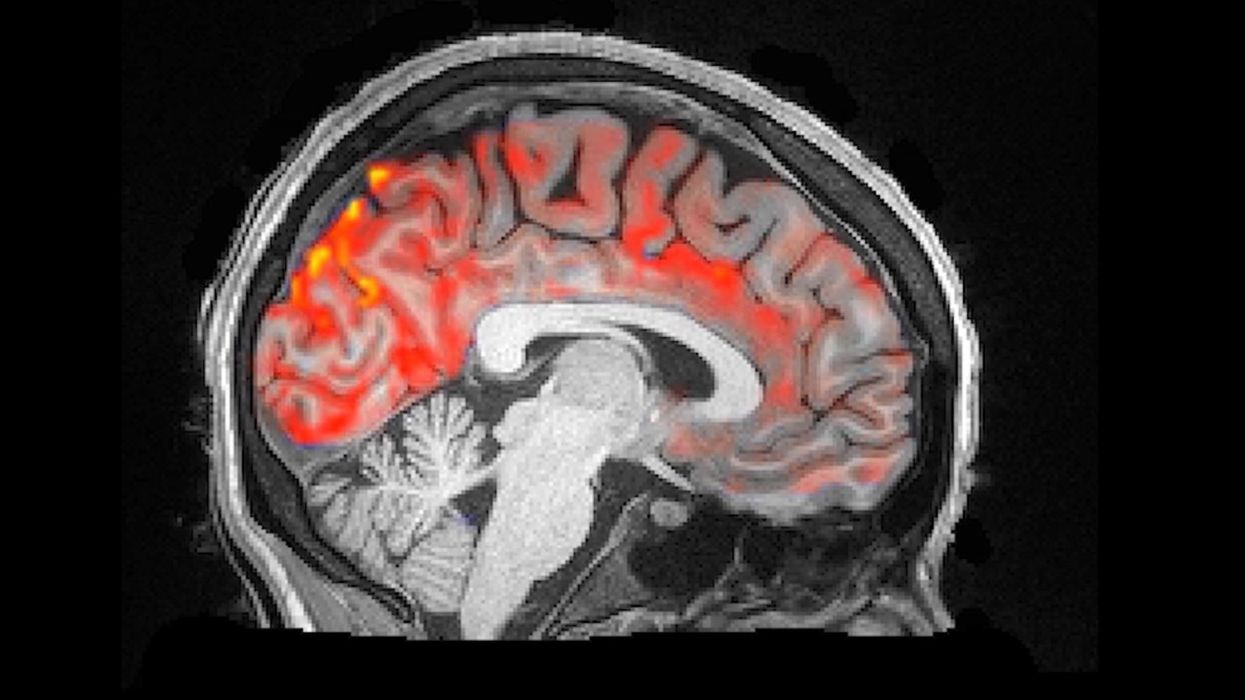

Neuro-shkencëtarët kanë bërë xhirim të mrekullueshëm në të cilin shihet pastrimi pulsues i aparatit tonë të trurit, shkruan Science Alert, transmeton Telegrafi.

Sipas hulumtimit më të ri, gjatë natës nëpër trurin tonë rrjedhin valët e lëngut cerebrospinalë, duke pulsuar ritmikisht derisa ne flemë gjumë dhe eliminojnë toksinën e dëmshme.